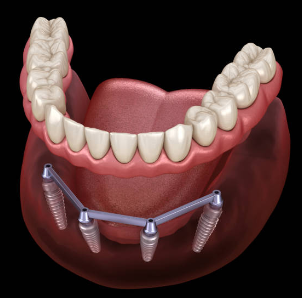

본래에는 인체의 조직이 상실되었을 때 이를 회복시켜 주는 대체 물질을 의미하지만, 치과에서는 인공 치아 이식의 의미를 지니기도 합니다. 이해를 쉽게 하기 위하여 다시금 말씀드리면, 인공적인 치아를 상실된 치아부위의 잇몸 뼈에 식립을 한 후, 그 위에 인공치아를 장착하여 수복하는 치료 방법을 말하는 것입니다.

2. 치아 발치 및 1차 시술

임플란트가 필요한 치아의 발치를 실시한 후, 그곳에 1차 시술을 진행합니다. 1차 시술은 턱뼈에 임플란트 인공치근을 식립하고 잇몸을 덮는 과정을 뜻하며, 이 과정에는 필수 기간이 필요하며 일정기간 동안 인공치근과 턱뼈가 잘 붙도록 기다려야 하는데, 일반적으로 아래턱은 약 2~3개월, 윗턱은 약 4~6개월 소요됩니다.

3. 2차 시술

인공치근이 잇몸뼈에 잘 자리 잡은 후, 덮어진 잇몸을 다시 열어 인공치근을 밖으로 노출시킵니다. 이때 진행하는 시술을 인공치근과 지대주를 연결하는 2차 시술이라 합니다. 지대주는 인공치근과 치아머리 크라운을 연결하는 기둥 역할을 하며, 2차 시술 후 잇몸이 완치되는데 약 1~2주 정도 걸립니다.